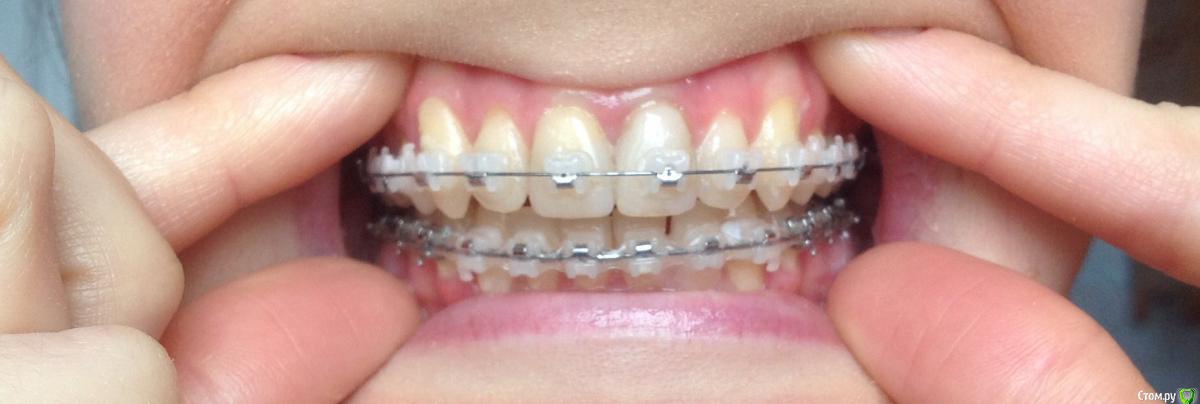

Добрый день ! Мне 29 лет. Ношу брекеты 10 мес. На данном этапе лечения сделали панорамный снимок, чтобы посмотреть ровно ли стоят корни зубов. После этого врач решил переклеить один брекет на клыке ( на снимке его видно слева ). А мне по снимку бросились в глаза , помимо этого клыка, рядом стоящий боковой резец ( он же не нравится мне как стоит и внешне) , и на нижней челюсти : 1- ый премоляр,и рядом стоящие 3 резца. Врач сказал подумать неделю и решить, хочу ли я переклеить или нет какой либо из брекетов,тк дальше они так и останутся. На её взгляд ничего переклеивать , кроме клыка, больше не нужно.

П.с. На нижн. челюсть уже поставили резинки для стягивания щелей. Я так понимаю после этого этапа уже на них брекеты не будут переклеиваться ?

Главный вопрос : Нужно ли мне переклеивать еще какие- нибудь брекеты , опускать или поднимать какой- либо из зубов, чтобы добиться большей эстетики и в дальнейшем правильного прикуса ? Или же не нужно. Заранее спасибо за внимание.